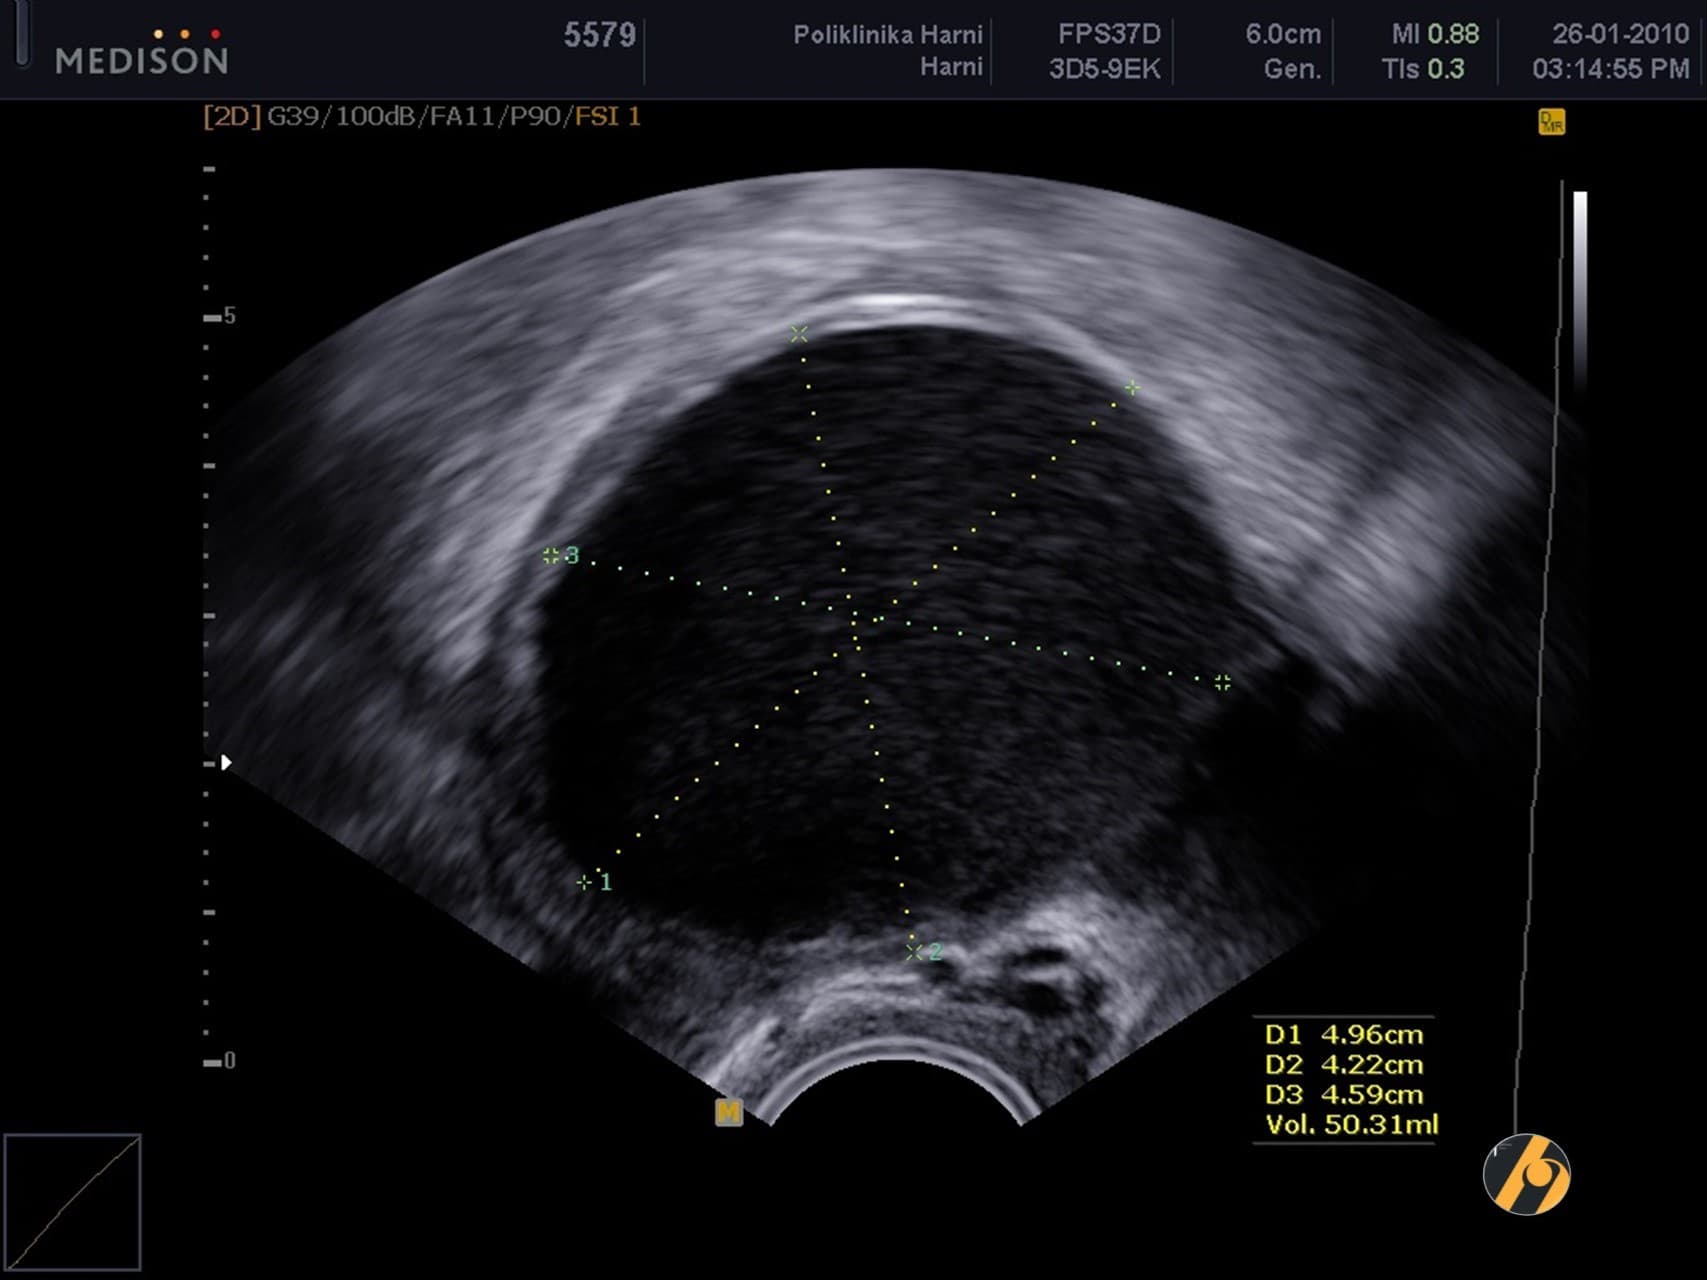

Premda su laparoskopija i patohistološka dijagnostika zlatni standard u dijagnostici endometrioze, u postavljanju dijagnoze od pomoći mogu biti i drugi manje invazivni postupci. Nažalost, ove tehnike kao što su transvaginalna sonografija i magnetska rezonancija nisu u stanju otkriti manje ili lezije koje su manje aktivne. Transvaginalna ultrazvučna dijagnostika učinkovito otkriva endometriotička žarišta čiji je promjer veći od 19 mm (¾ incha).